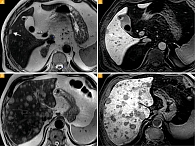

Рис. 1. Метастазы увеальной меланомы в печень: А (на Т2-ВИ) и Б (Т1-ВИ) с контрастным усилением, гепатобилиарная фаза – визуализируется единичный очаг в правой доле печени (стрелка); В (Т2-ВИ) и Г (Т1-ВИ) с контрастным усилением

Размеры очагов варьировали от 2 до 78 мм (средний размер очага 4,5 мм). Единичные очаги (до 4 мм) выявлены у четырех пациентов (рис. 1А, 1Б), множественные очаги – у семи (рис. 1В, 1Г). Множественные очаги визуализировались в обеих долях печени, единичные – в правой доле.

При нетипичных для метастазов характеристиках выполнение гепатоспецифической фазы позволило дать более точное представление о природе подозрительных очагов. Отсутствие накопления контрастного вещества в отсроченную фазу в подозрительных очагах свидетельствует об отсутствии в них гепатоцитов (рис. 1).